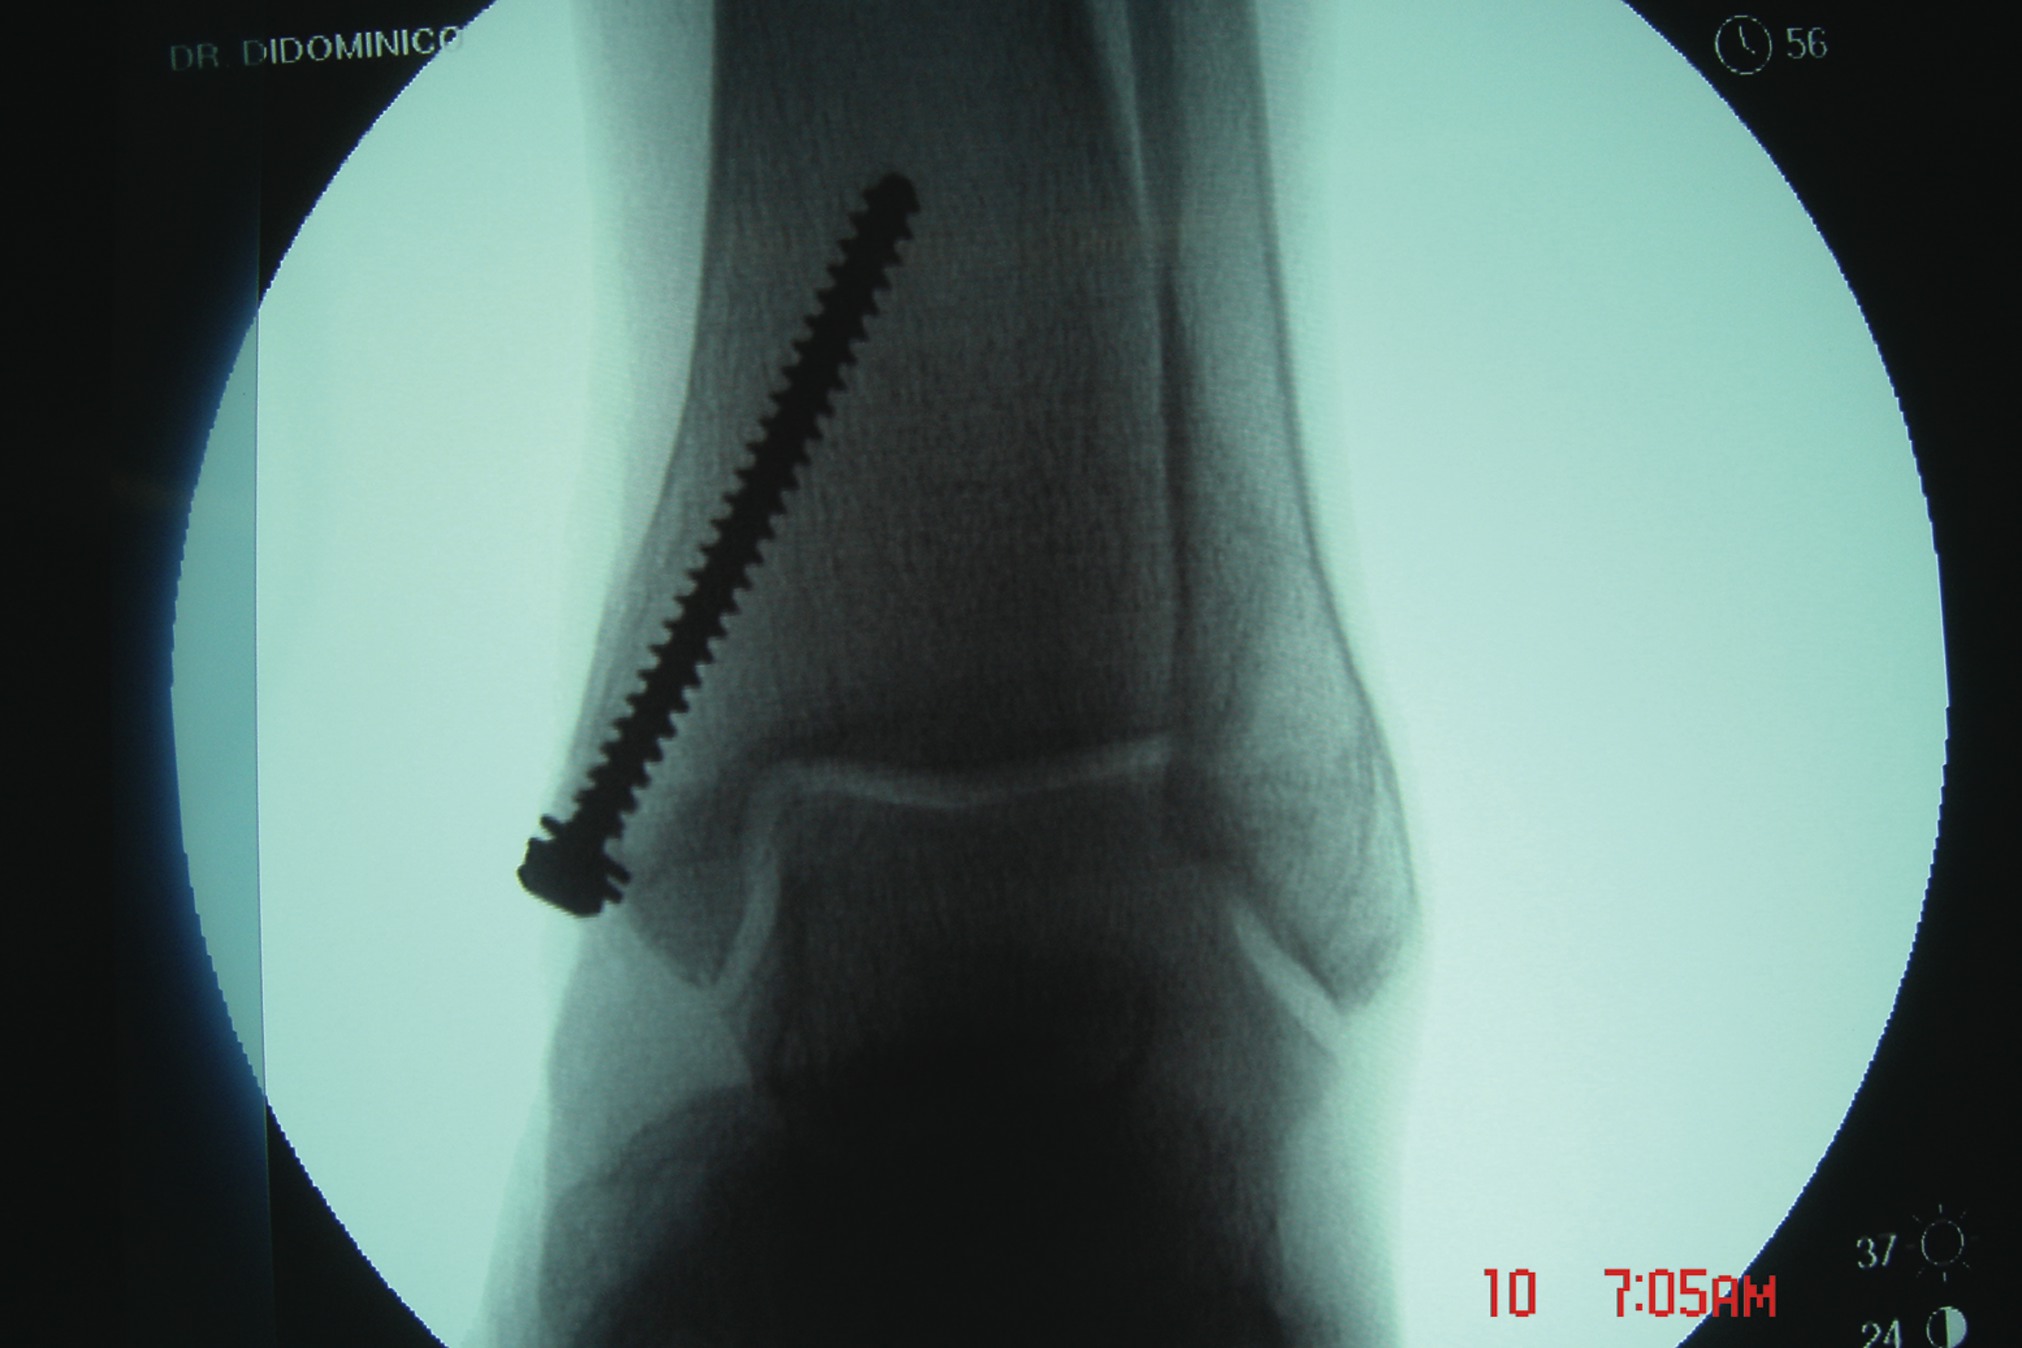

All athletes, regardless of the level of performance, will need the appropriate physical therapy modalities and rehabilitative techniques to complete functional recovery from an ankle fracture. Athletes who are at the competitive amateur level or professional level will need to return to their performance level sooner than the weekend warrior. Athletes whose career is based on their performance and return to competition will need complete rehabilitation. These individuals have no financial constraints as compared to some amateur athletes and recreational athletes. There are three phases of rehabilitation: the acute phase, the recovery phase and the functional phase. Phase one is the reduction of pain, inflammation and edema while retarding muscle atrophy of the lower extremity complex. Improving range of motion is also a major component in this acute phase. Phase two involves improving range of motion, improving lower extremity strength, increasing neuromuscular control and regaining normal arthrokinematics (defined as function of the joint) in single planes and triplanar motion of the ankle. Phase three involves increasing power of the lower extremity complex, increasing neuromuscular control in multiple planes of motion and utilizing sport-specific training for a full return to sport.30,31 A consideration with treating athletes is that if the athlete is inactive after his or her injury, the athlete loses training adaptation. This means the athlete will “detrain” as the individual’s physiological function reverts to the normal untrained state.32 It is most essential that the athlete remain active in some form of alternative exercise or maintenance program during the rehabilitative period in order to maintain his or her mental and physical strength. Alternative activities include water running and weight training of the upper extremity and the noninvolved lower extremity. Any form of maintaining aerobic capacity, neuromuscular coordination and muscle strength will help reduce injury.30 When it comes to ankle fractures in competitive athletes who require full function of their joints and motion, these individuals will need complete reduction with no malalignment. In previous studies, authors have shown that 1 to 2 mm of displacement of the fibula can cause an increase in tibiotalar contact up to 42 percent. This can lead to increased arthrosis and pain, which can reduce the longevity of playing careers.33 The trend is to perform open reduction and internal fixation of the fracture for early mobilization/rehabilitation, especially when it comes to early season injuries and reducing recovery time in order to facilitate a return to mid-season or end of the season play.7 If an injury occurs at the end of the season, the goal is getting an athlete fully rehabilitated for offseason training. If the podiatrist manages the athlete surgically with open reduction and internal fixation, one may have the patient begin early partial weightbearing in a walking boot with passive range of motion exercises at one to two weeks postoperatively. If you are treating professional athletes or high level college athletes, one may utilize bone stimulation in the postoperative management regimen to increase healing time. The athlete can begin physical therapy at two weeks postoperatively with phase one of rehabilitation exercises. The first phase of rehabilitation will include passive range of motion exercises and cryotherapy, which clinicians can initiate immediately after surgery by having the patient wear circulating cryotherapy boots at the hospital or surgery center. After the patient has met the goals of the first phase of rehabilitation, one may proceed to the second phase, which is usually initiated at three to four weeks postoperatively. One must remember to use pain as a guide in dealing with any type of rehabilitation procedure. In the second phase, patients may initiate strengthening with Theraband, range of motion exercises and proprioception exercises with a biomechanical ankle platform system (BAPS). Advise these patients that when they use theraband, they should use the least resistant bands initially. Toward the end of the second phase, the athlete should begin using a wobble board to improve proprioception and begin closed kinetic chain activities such as walking and loading. In the sixth to eighth week post-op, the athlete should begin the third phase of rehabilitation, which involves improving power, increasing neuromuscular control and utilizing sport-specific training of the lower extremity for a full return to sport.31 In the functional phase of rehabilitation, one may initiate plyometric (defined as “used to restore force”) exercises such as double-leg jumping, single leg jumping, four-square hopping, use of a minitramp and running to cutting progressions.30,31 The athlete should continue neuromuscular exercises and leg control exercises in this phase as well. The hip and leg control exercises involve hip and knee strengthening, one-legged stance and agility drills. Sport-specific exercises involving jumping, cutting and kicking offer a final component to the rehabilitation process.31 In regard to the various physical therapy modalities, such as iontophoresis, ultrasound, contrast bathing and interferential stimulation, one should continue utilizing these modalities to reduce swelling, pain and improve motion. Protecting the injured extremity will be very important in the later stages of rehabilitation with taping and bracing. When the athlete returns to full speed activity, he or she should continue to utilize a supportive device indefinitely.